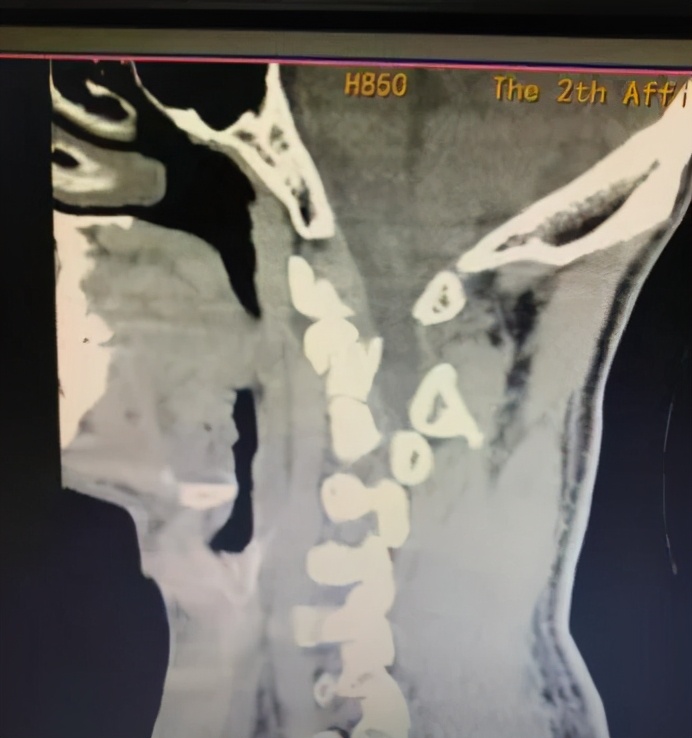

一个月前,广州医科大学附属第二医院接诊了两位高位颈椎骨折患者。当时,吴先生开摩托车载着杨先生外出,不慎遭车祸。 检查发现,二人均为颈椎粉碎性骨折,且性质极不稳定。

高位颈椎骨折内固定手术是一项难度高、风险大的手术。因手术位置特殊、解剖关系复杂,术中操作空间有限,稍有不慎将损伤颈髓、神经根,出现高位截瘫或者损伤重要血管,甚至危及生命。骨科主任曹燕明教授坦言,“吴先生和杨先生都属于高位颈椎骨折,骨折与血管、神经根、脊髓紧密相邻,术中误伤风险高,手术难度高。”

为了能精准地呈现患者椎体和神经等状况,更直观地了解病情,降低手术风险,曹燕明团队决定在术前借助3d打印技术, 1:1地打印出患者“仿真颈椎”进行手术预演。

▲颈椎模型

据了解,目前3D打印技术已广泛应用于临床,腰椎、胸椎、颈椎等骨科手术。术前根据3D打印模型可以更直观地了解骨折细节,推演手术操作中潜在的困难,从而可以选择最佳的手术方案,降低手术风险。